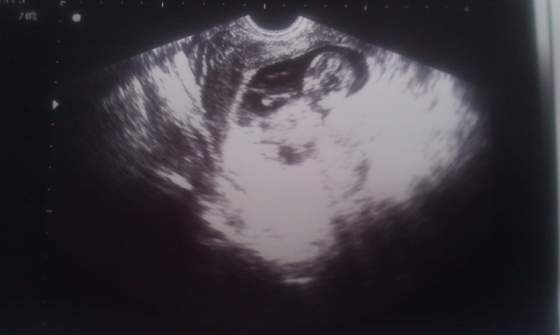

IMAG0161.jpgIMAG0163.jpgIMAG0162.jpgto moje maleństwo dzisiaj 6 cm(ale ma malusia raczke) ; ))) a później mój brzuszek dzisiaj ; ) anisen super kosmita mały masz takie fajne wyraźne zdjęcia ; )))

USg mój gin ma naprawdę dobre :) do tego jeden monitor dla gina drugi dla mnie i męza ;) nie muszę zaglądać do góry bo mam tak ze tylko glowę odwracam i na 24 calach obraz maleństwa :)